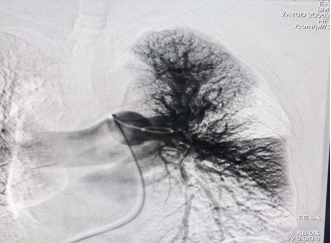

第二,开展新技术新业务,填补彭水县的医疗领域的空白。与彭水血管外科团队通力合作,先后开展了主动脉夹层腔内隔绝术,肺动脉造影吸栓术各1例,手术效果良好,患者均已康复出院,回访患者恢复良好。

典型病例资料2: